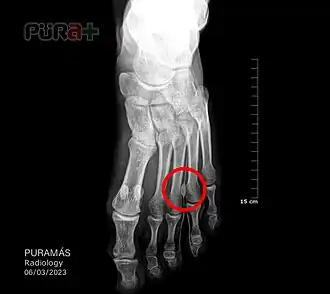

El neuroma de Morton es un engrosamiento del nervio interdigital en el espacio que existe entre el tercer y cuarto dedo del pie. Se produce como consecuencia de una compresión crónica con gran énfasis en el tercero y cuarto dedo o falange (en el 75% de los casos) o entre el segundo o tercero (en el 17% de los casos). Provoca dolor a veces muy intenso en la zona anterior de la planta del pie, a nivel del metatarso.[1]

- Rayos X o Rx para descartar enfermedades óseas.